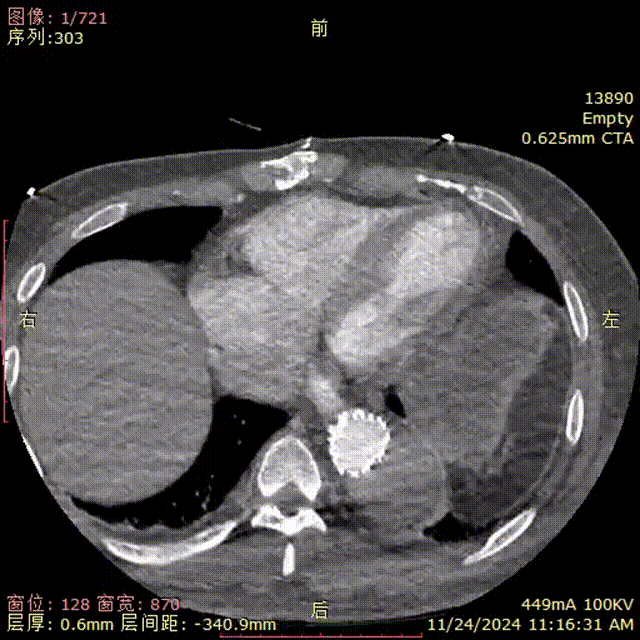

患者术后复查,CTA显示支架形态良好,弓上分支血流通畅。

gore医疗怎么样「胸有乾坤」强弓硬弩 一蹴而就——CTAG弓上三开窗治疗主动脉夹层病例报道_https://www.jmylbn.com_新闻资讯_第18张

术后复查CTA